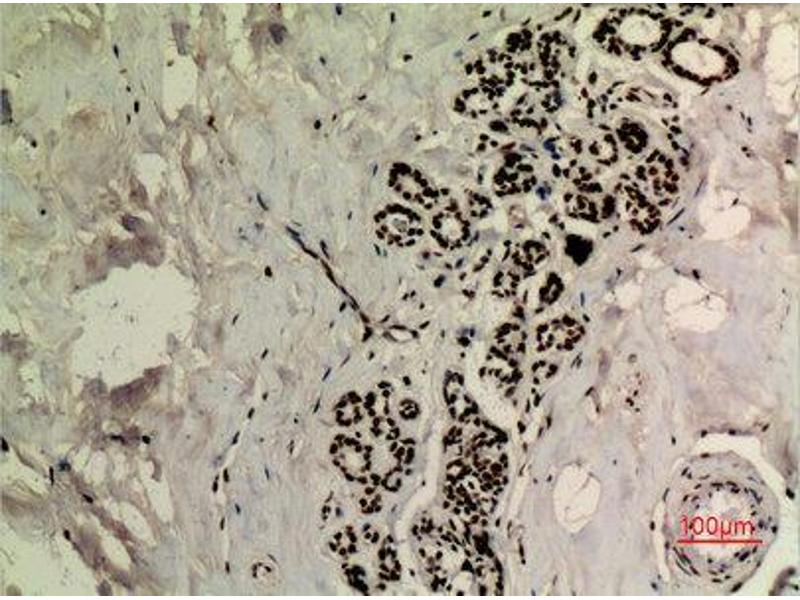

TP53 Reaktivität: Human, Maus ELISA, FACS, IHC (p), IF (p), IF (cc), IHC (fro) Wirt: Kaninchen Polyclonal unconjugated

Pubmed 3 Referenzen

Produktnummer ABIN729763